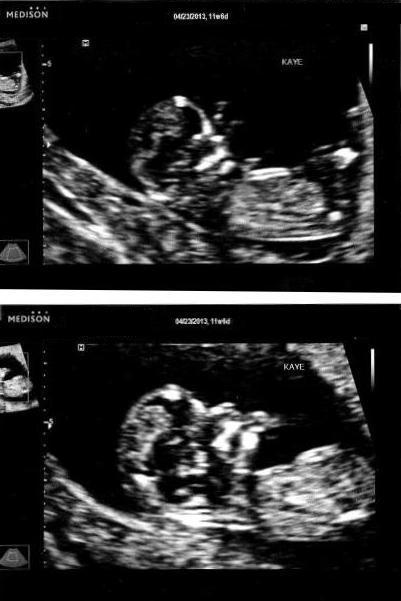

Girl

boy!

Just thought I'd update this for future reference: IT'S A GIRL!